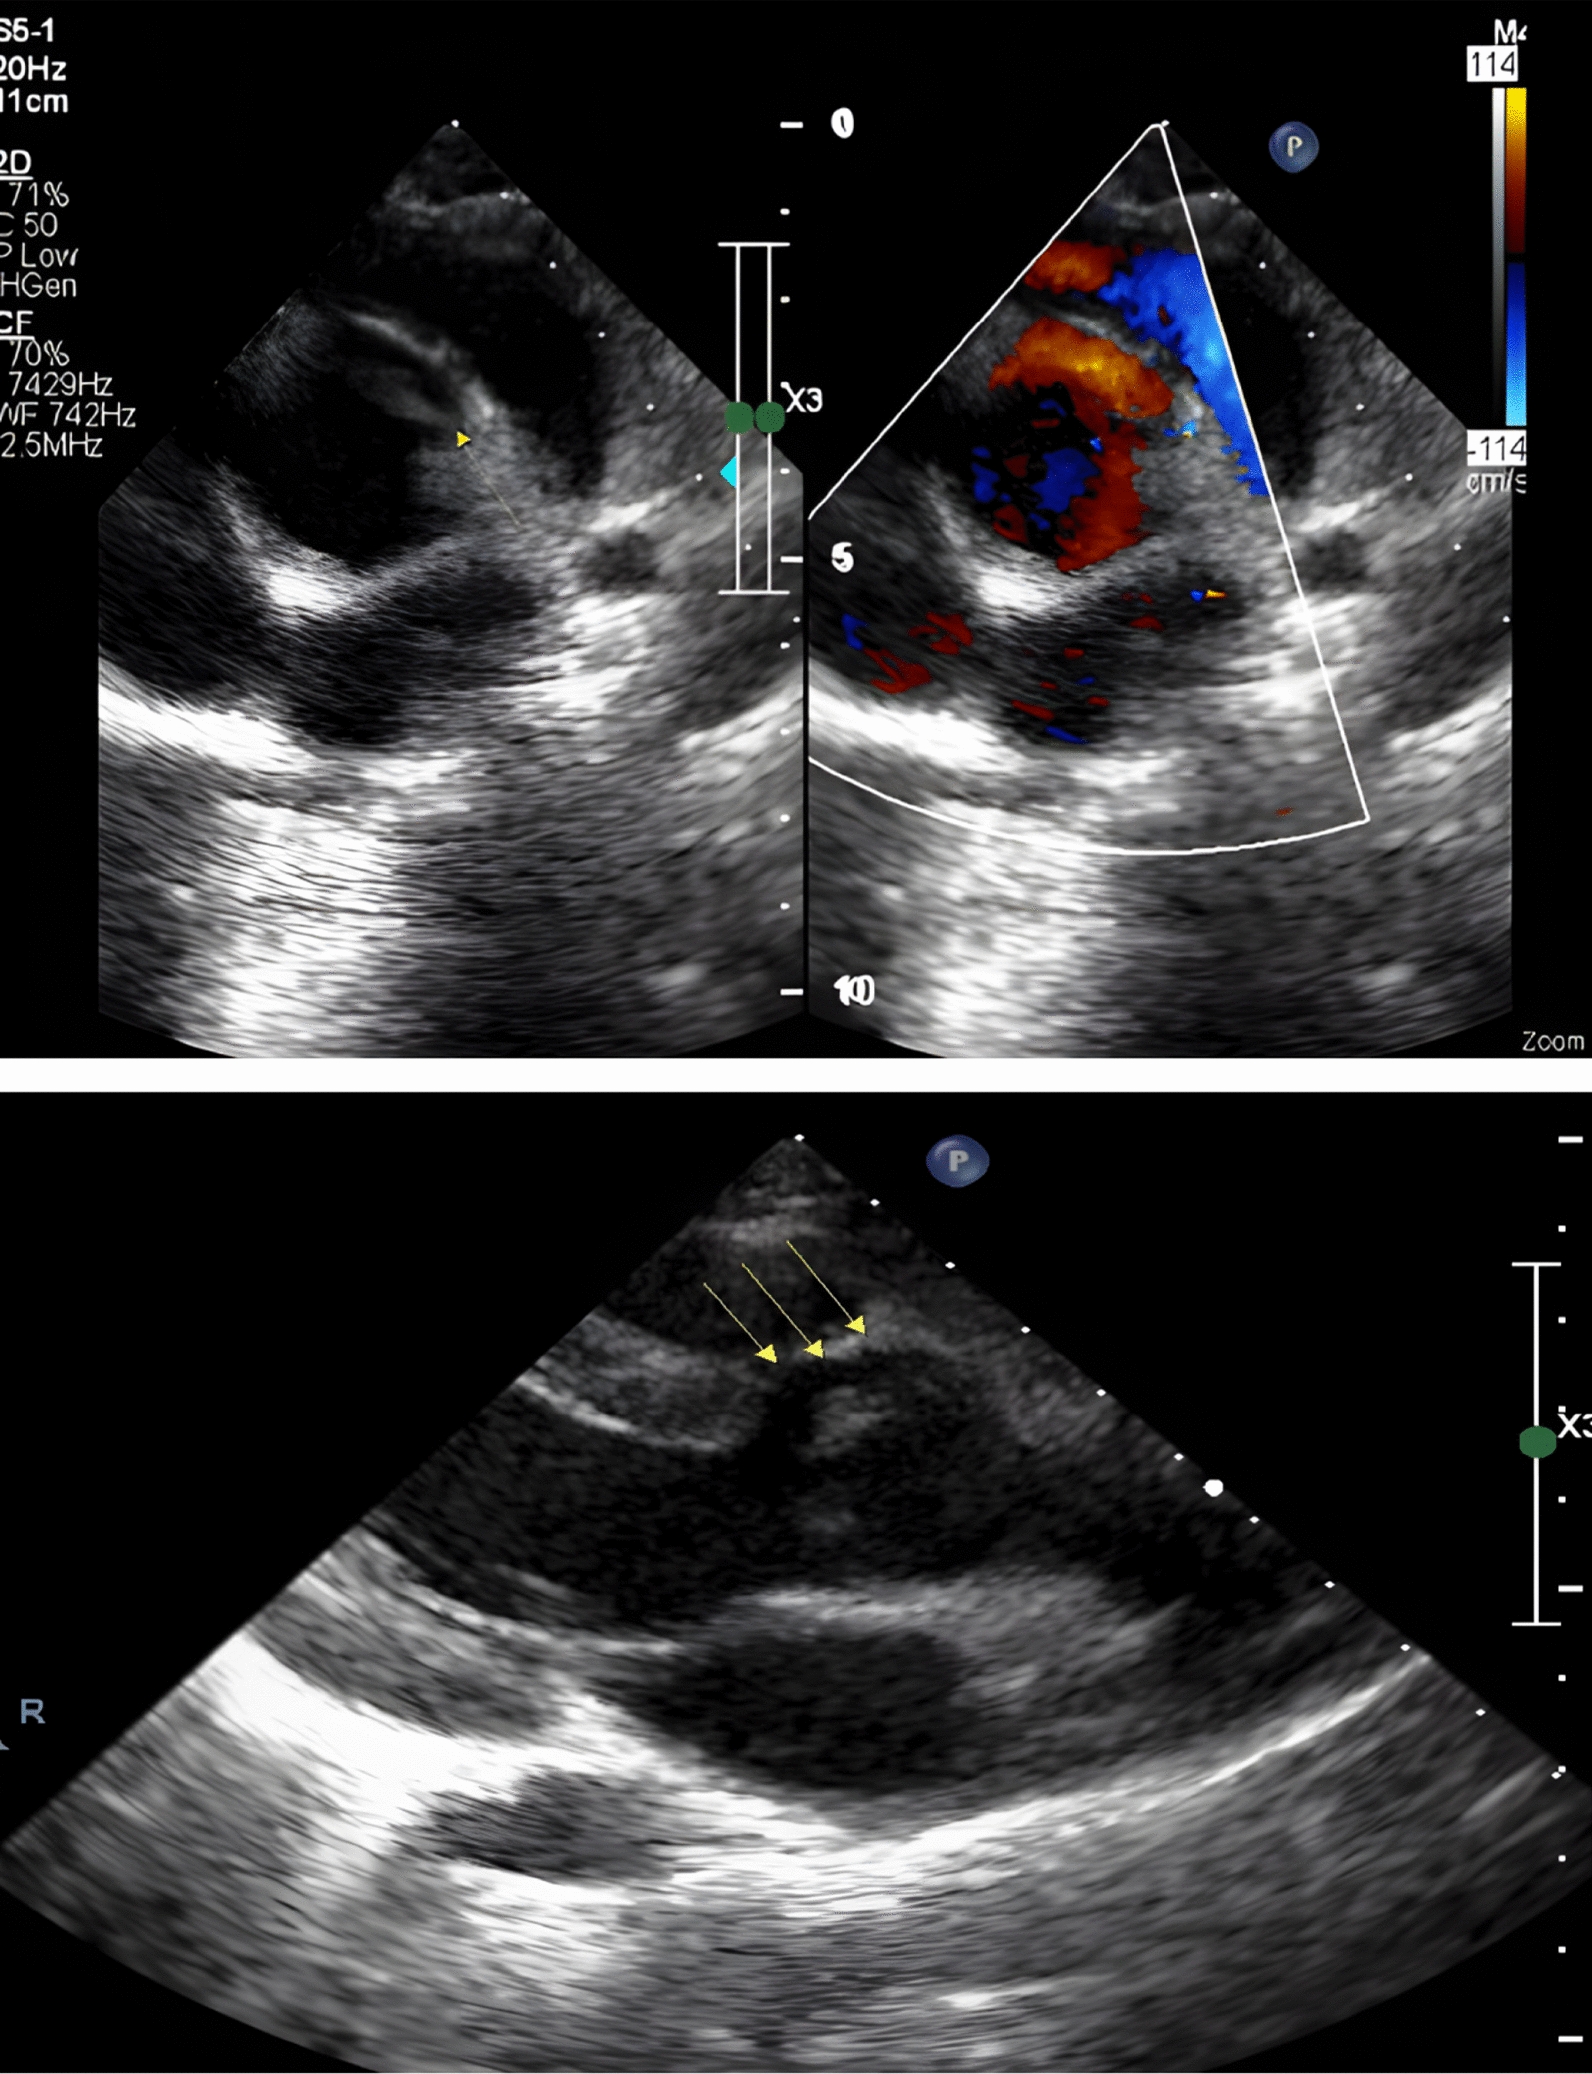

Myxomatous cause of multiple intracranial aneurysms and cognitive decline: a case report

Cardiac myxoma is a tumour of mesenchymal origin comprising almost half of all primary cardiac tumours [4]. As many as 10% of patients with atrial myxoma remain asymptomatic. They usually present with systemic embolism, intracardiac obstruction, constitutional symptoms and rarely with arrhythmia or acute coronary syndrome (Table 1) [5, 6]. Acute ischaemic stroke is the most common neurological sequel secondary to tumour embolism, and others include intracranial aneurysms, vascular malformation and parenchymal metastases [7]. In a recent systematic review of 55 patients with atrial myxomas and intracranial aneurysms described to date, the majority were females (65%) and young (age < 60 years, 86%) [3, 8]. Aneurysms were detected before, during or even 25 years after the diagnosis/resection of the atrial mass [3].

Cognitive disturbance is an uncommon presentation in atrial myxomas which can be due to recurrent infarcts or bleeding from aneurysms. Our patient presented with cognitive decline secondary to recurrent subcortical infarcts caused by myxomatous embolism which could have been averted had she undergone evaluation for her stroke earlier. Digital subtraction angiogram showed multiple aneurysms at distal branches which were predominantly fusiform, the aetiology of which can be attributed to myxoma in the absence of other risk factors or genetic morphology for aneurysms.